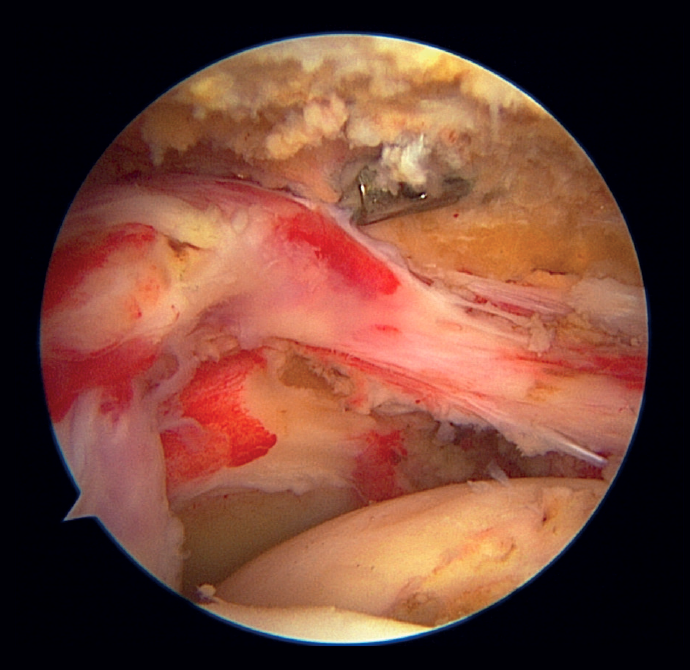

Different definitions of massive rupture of the rotator cuff (MRRC) have been proposed over time. Cofield defined them as lesions measuring 5 cm or more in diameter(6), while according to Gerber et al.(7) they involve the complete deinsertion of two or more tendons, exposing the tuberosities - a circumstance easily identifiable during surgery (Figure 1). On the other hand, Davidson and Burkhart(8) defined such lesions as retracted ruptures measuring at least 2 cm in length in the sagittal plane and with a width of 2 cm in the coronal plane - being identifiable preoperatively by means of magnetic resonance imaging (MRI). However, these definitions may result in bias due to differences in size between patients or the position of the arm at the time of measurement, and they moreover fail to distinguish between different patterns of rupture and do not predict function of the injured shoulder. Accordingly, Ladërmann et al.(9) considered that in addition to the number of damaged tendons, at least one of the two must be retracted more medial to the humeral head - this corresponding to supraspinatus grade 3 retraction in the coronal plane according to the classification of Patte(10), which adds more objective three-dimensional value to the measurement (Figure 2). Lastly, Schumaier et al., involving a group of experts, recently published a consensus document defining massive ruptures as those that are retracted to the margin of the glenoid cavity in the coronal or axial plane and/or present exposure of two-thirds of the greater tuberosity footprint in the sagittal plane(11).